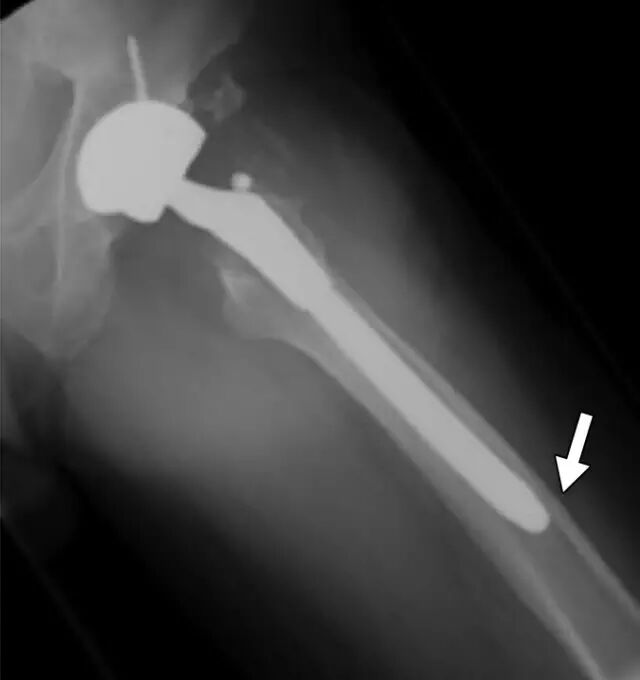

一旦确定了骨折,放射科医生应对其进行表征,以便进一步管理。然而,可能存在放射科医师可以提供超出简单骨折描述的范围的更多信息。特定解剖部位的骨折在特定年龄通常更频繁,并且通常作为特定机制的结果而发生。识别对于部位,年龄和机制不典型的骨折应导致进一步调查。例如,由于大的创伤性事件(例如机动车辆撞击或从高处坠落),近侧股骨轴(转子间或转子间 - 转子间)的骨折通常发生在健康成年人中。近端股骨干骨折可能由于在具有骨骼脆性的非常老年人群中或在具有使骨骨折的某些潜在病症的群体中的地面下降而发生。因此,由于地面跌倒导致的年轻或中年成年人的股骨近端骨折的发现应该引起立即怀疑潜在的预处置状况。经常有关于初始创伤X光片的潜在病理生理学的线索。外侧股骨皮质的增厚,特别是如果存在三角形峰的外观,已被认为是二膦酸相关的不全性骨折的特征[41](图10)局部的骨质破坏可以指示肿瘤或骨髓炎的存在。近端股骨是骨转移的最常见部位[42]。特别是,成年人的小转子股骨骨折的存在应引起强烈的临床关注,由于转移性疾病的病理性骨折[43,44]。该信息对于临床医生在手术治疗中是有价值的。

骨折评估在硬件放置后的患者中是具有挑战性的,例如由于各种原因的骨折固定或关节置换所见[45,46]。密集重叠的金属密度可以限制硬件骨折或假体周围骨折的可视性。倾斜视图通常是有帮助的。诸如CT或MRI的横截面成像可以受到金属伪影的限制,并且应当在可用时使用修改的金属伪影减少协议来执行。硬件植入物改变宿主骨上的应力,导致应力屏蔽发生时的慢性骨丢失和应力集中的骨肥大。当经受创伤时,力倾向于集中在植入物和骨之间界面的位置。断裂通常在那些界面处开始,然后远离集中点传播。例如,髋关节植入物患者中的股骨骨折通常穿过股骨柄的尖端(图11)。通过具有内固定的骨的骨折通常穿过板的末端处的皮质。

图11A、B -54岁左侧全髋关节置换术的男性。A,骨盆正位片(A)和左侧髋部青蛙侧视图(B)显示股骨中轴延伸到股骨柄尖水平的倾斜骨折(箭头B)。